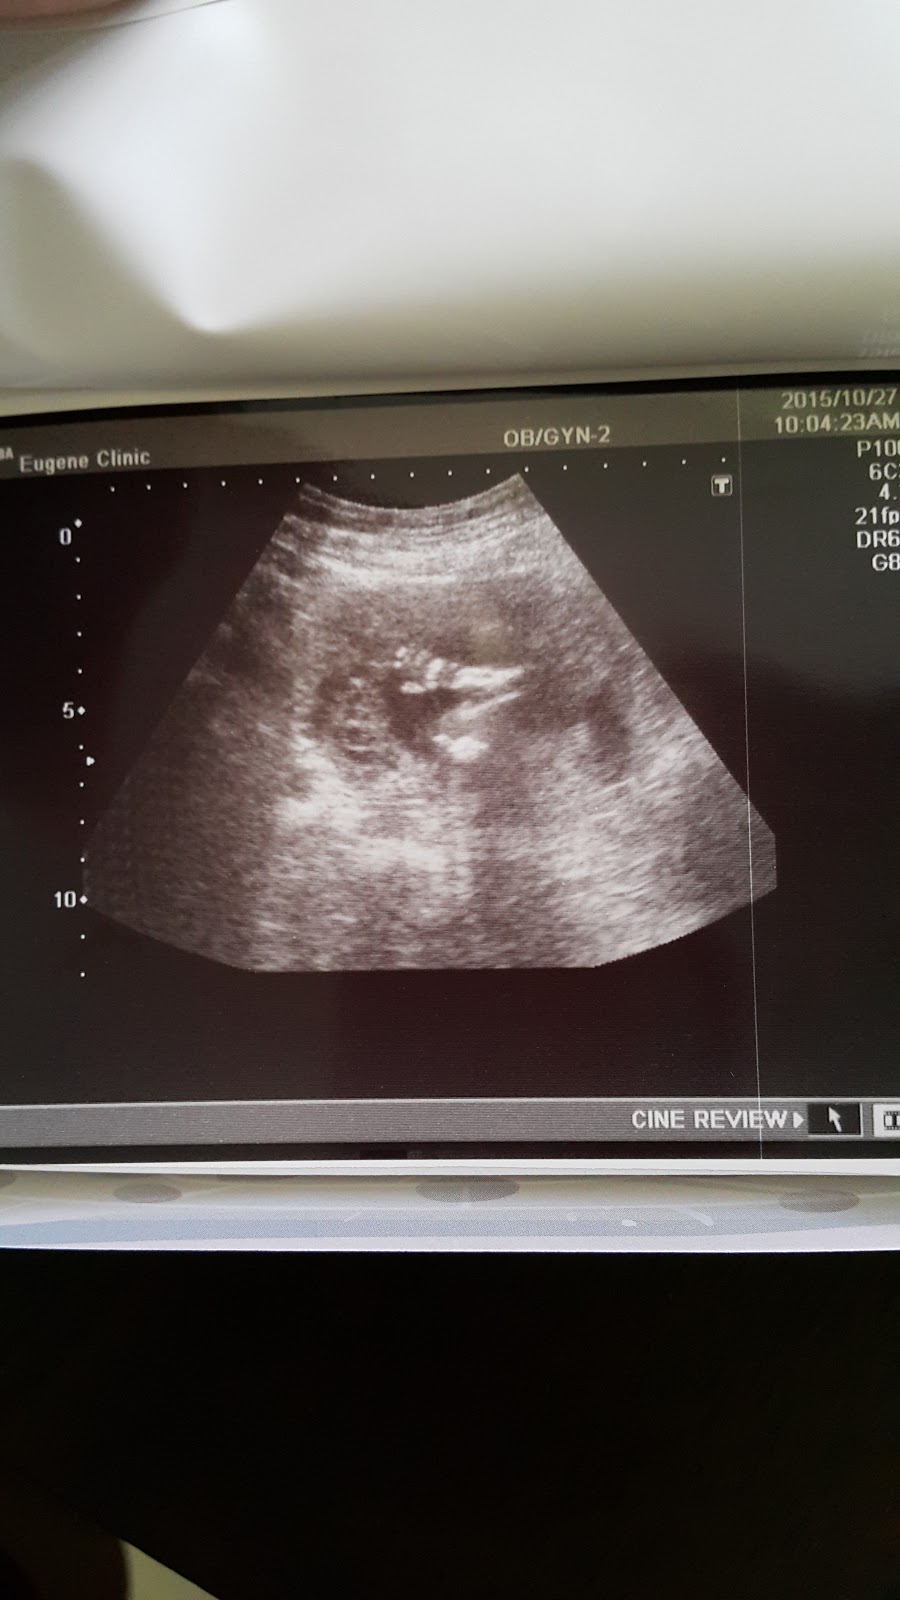

看著照音波照片,不由自主的笑出來

看著照音波,Haru有在好好長大

還看到他的小手打招呼

跟第一胎的哥哥一樣,拍到可愛的小手

這個時候大約可以照到性別了

其實週數還有點小,醫生轉了很久說,百分之七十是女生